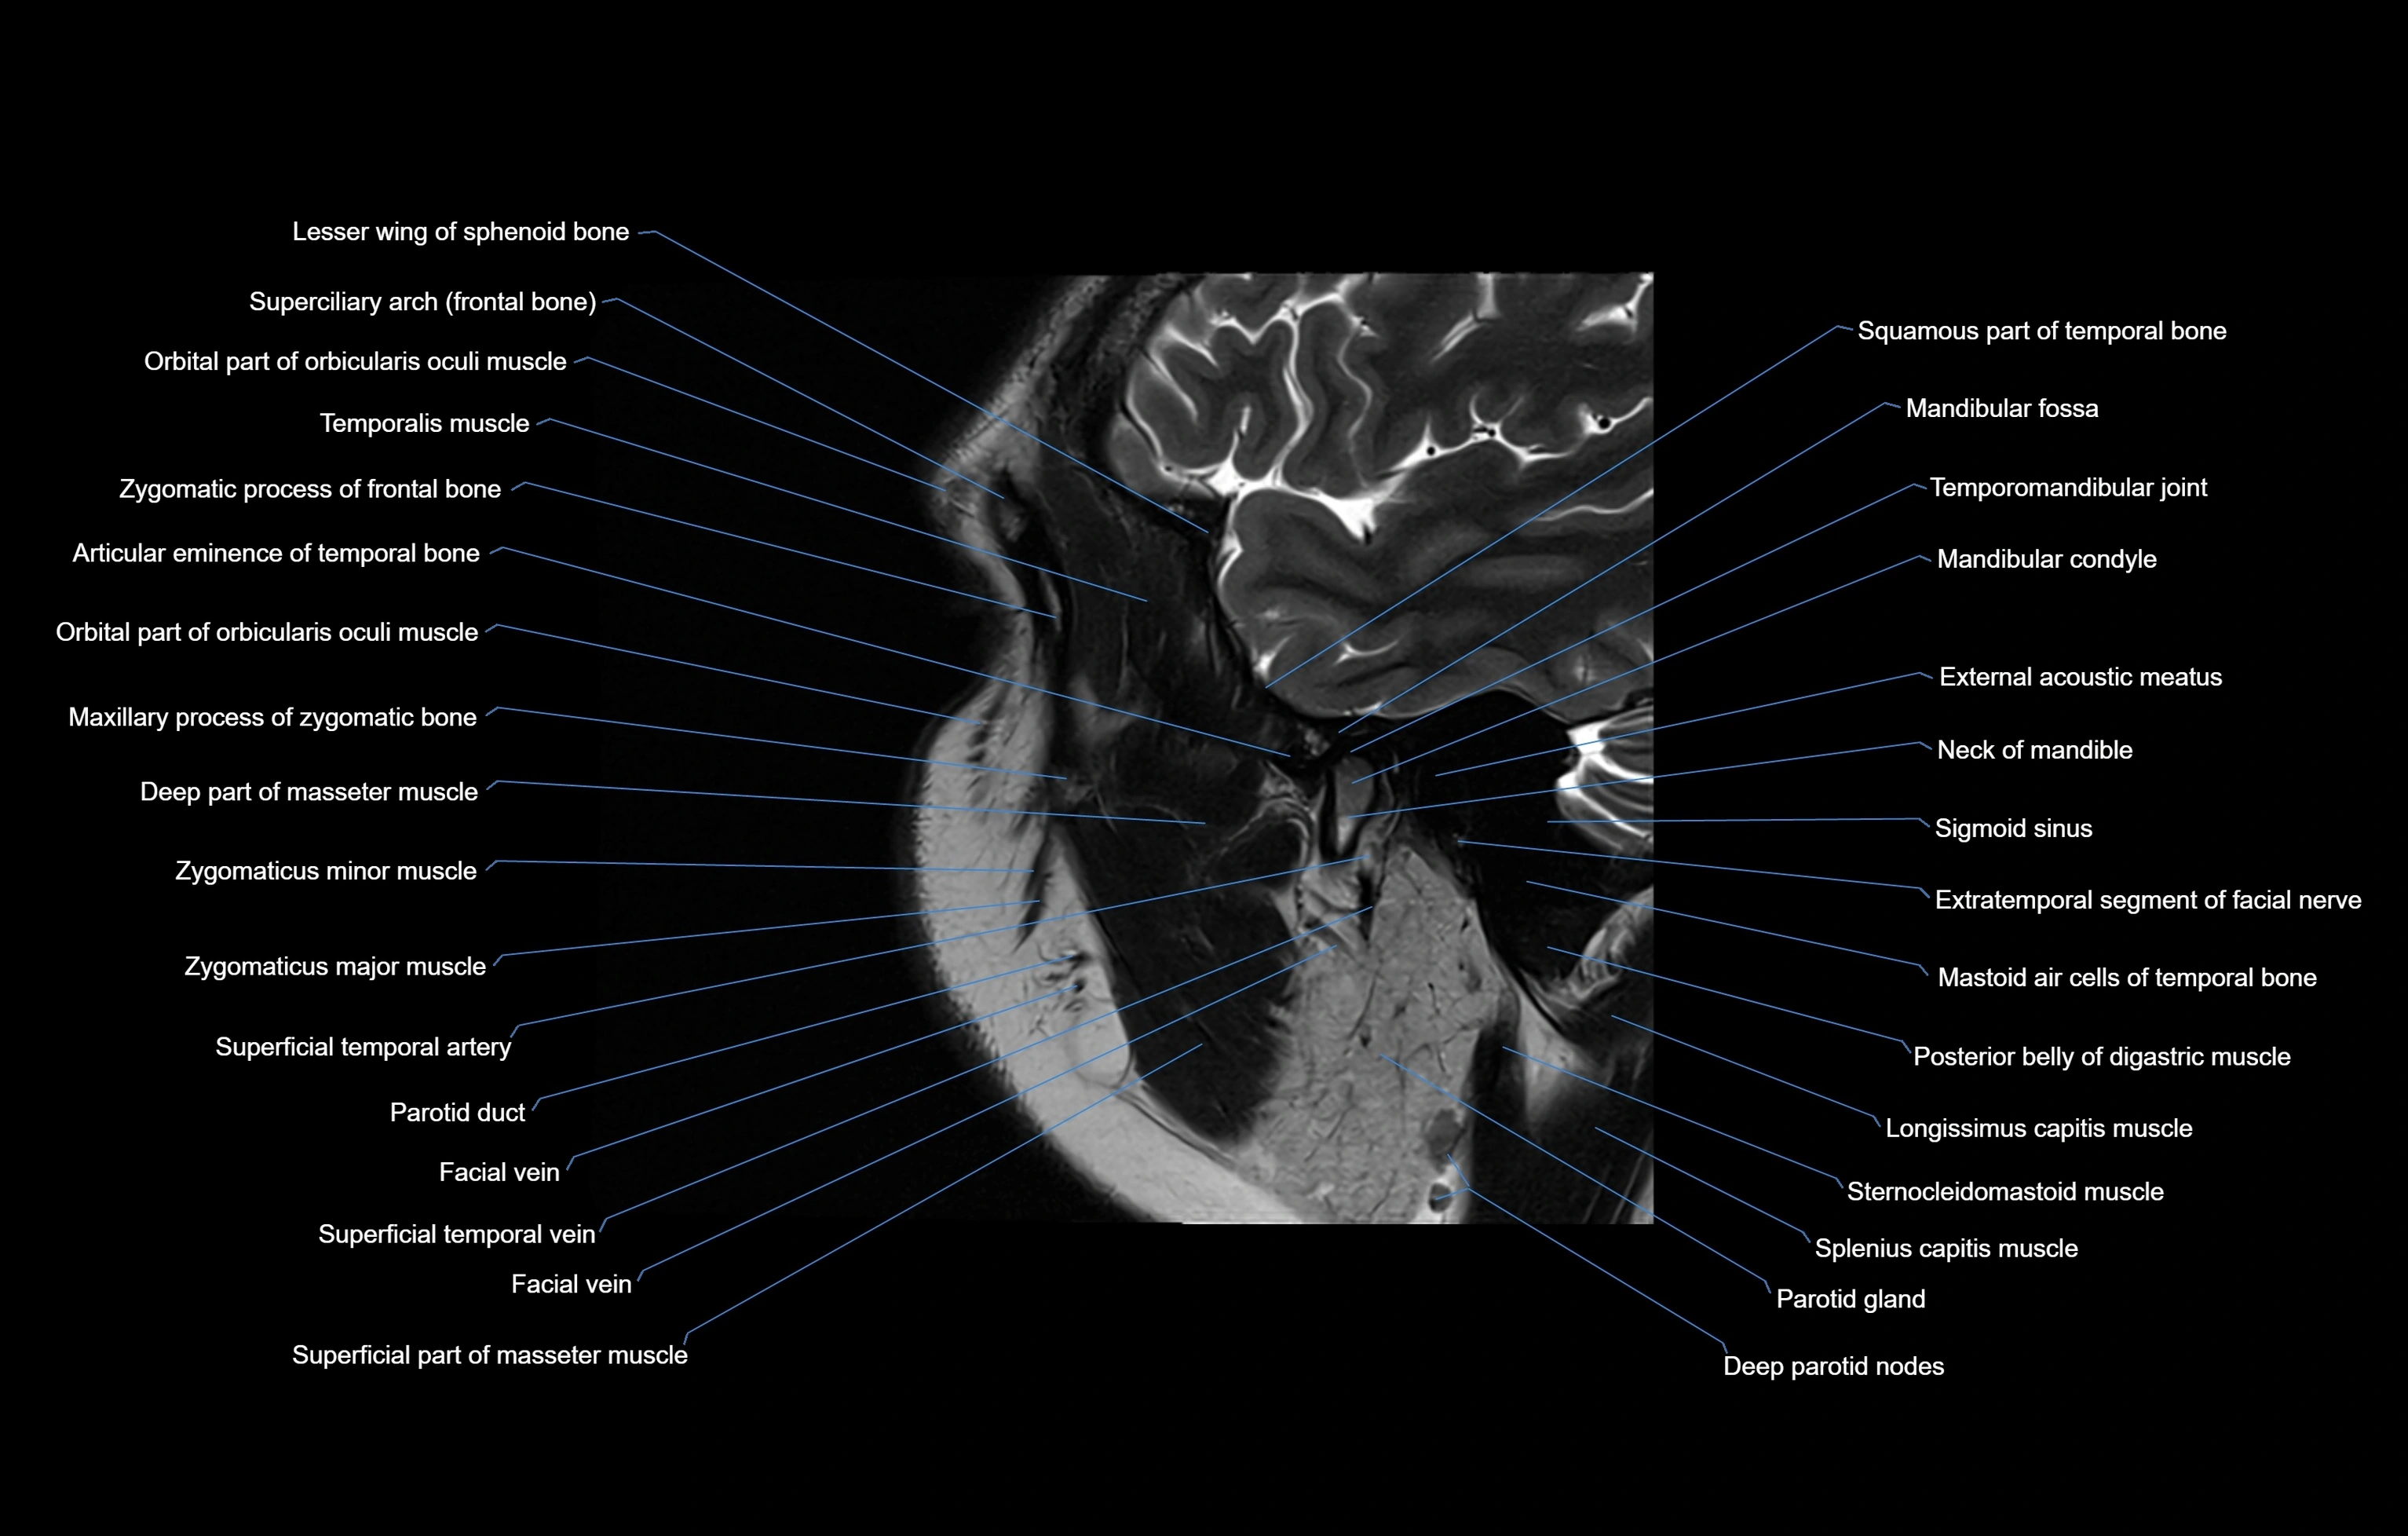

MRI images